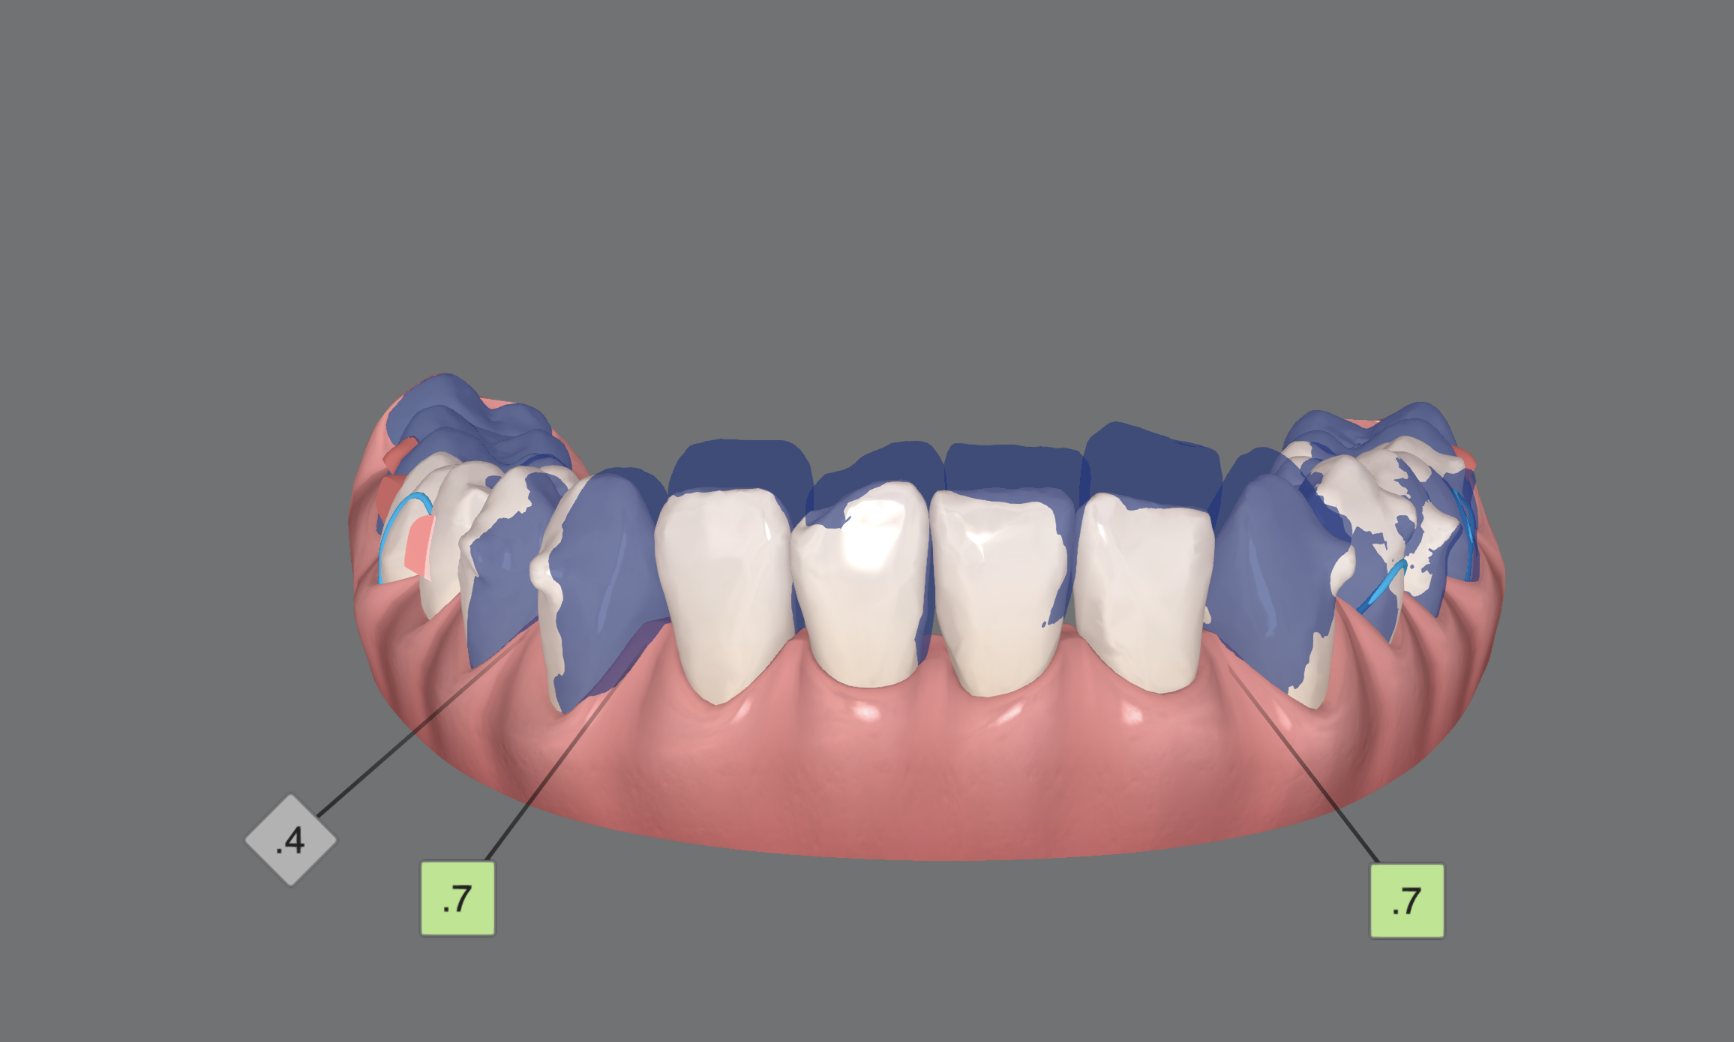

Además de esto, planificar la intrusión con espacios interdentales de 0,1 o 0,2mm reduce la fricción entre las piezas y mejora los resultados de manera sencilla, sobre todo en casos en los que hemos planificado stripping, el cual no siempre realizamos con una precisión del 100%.